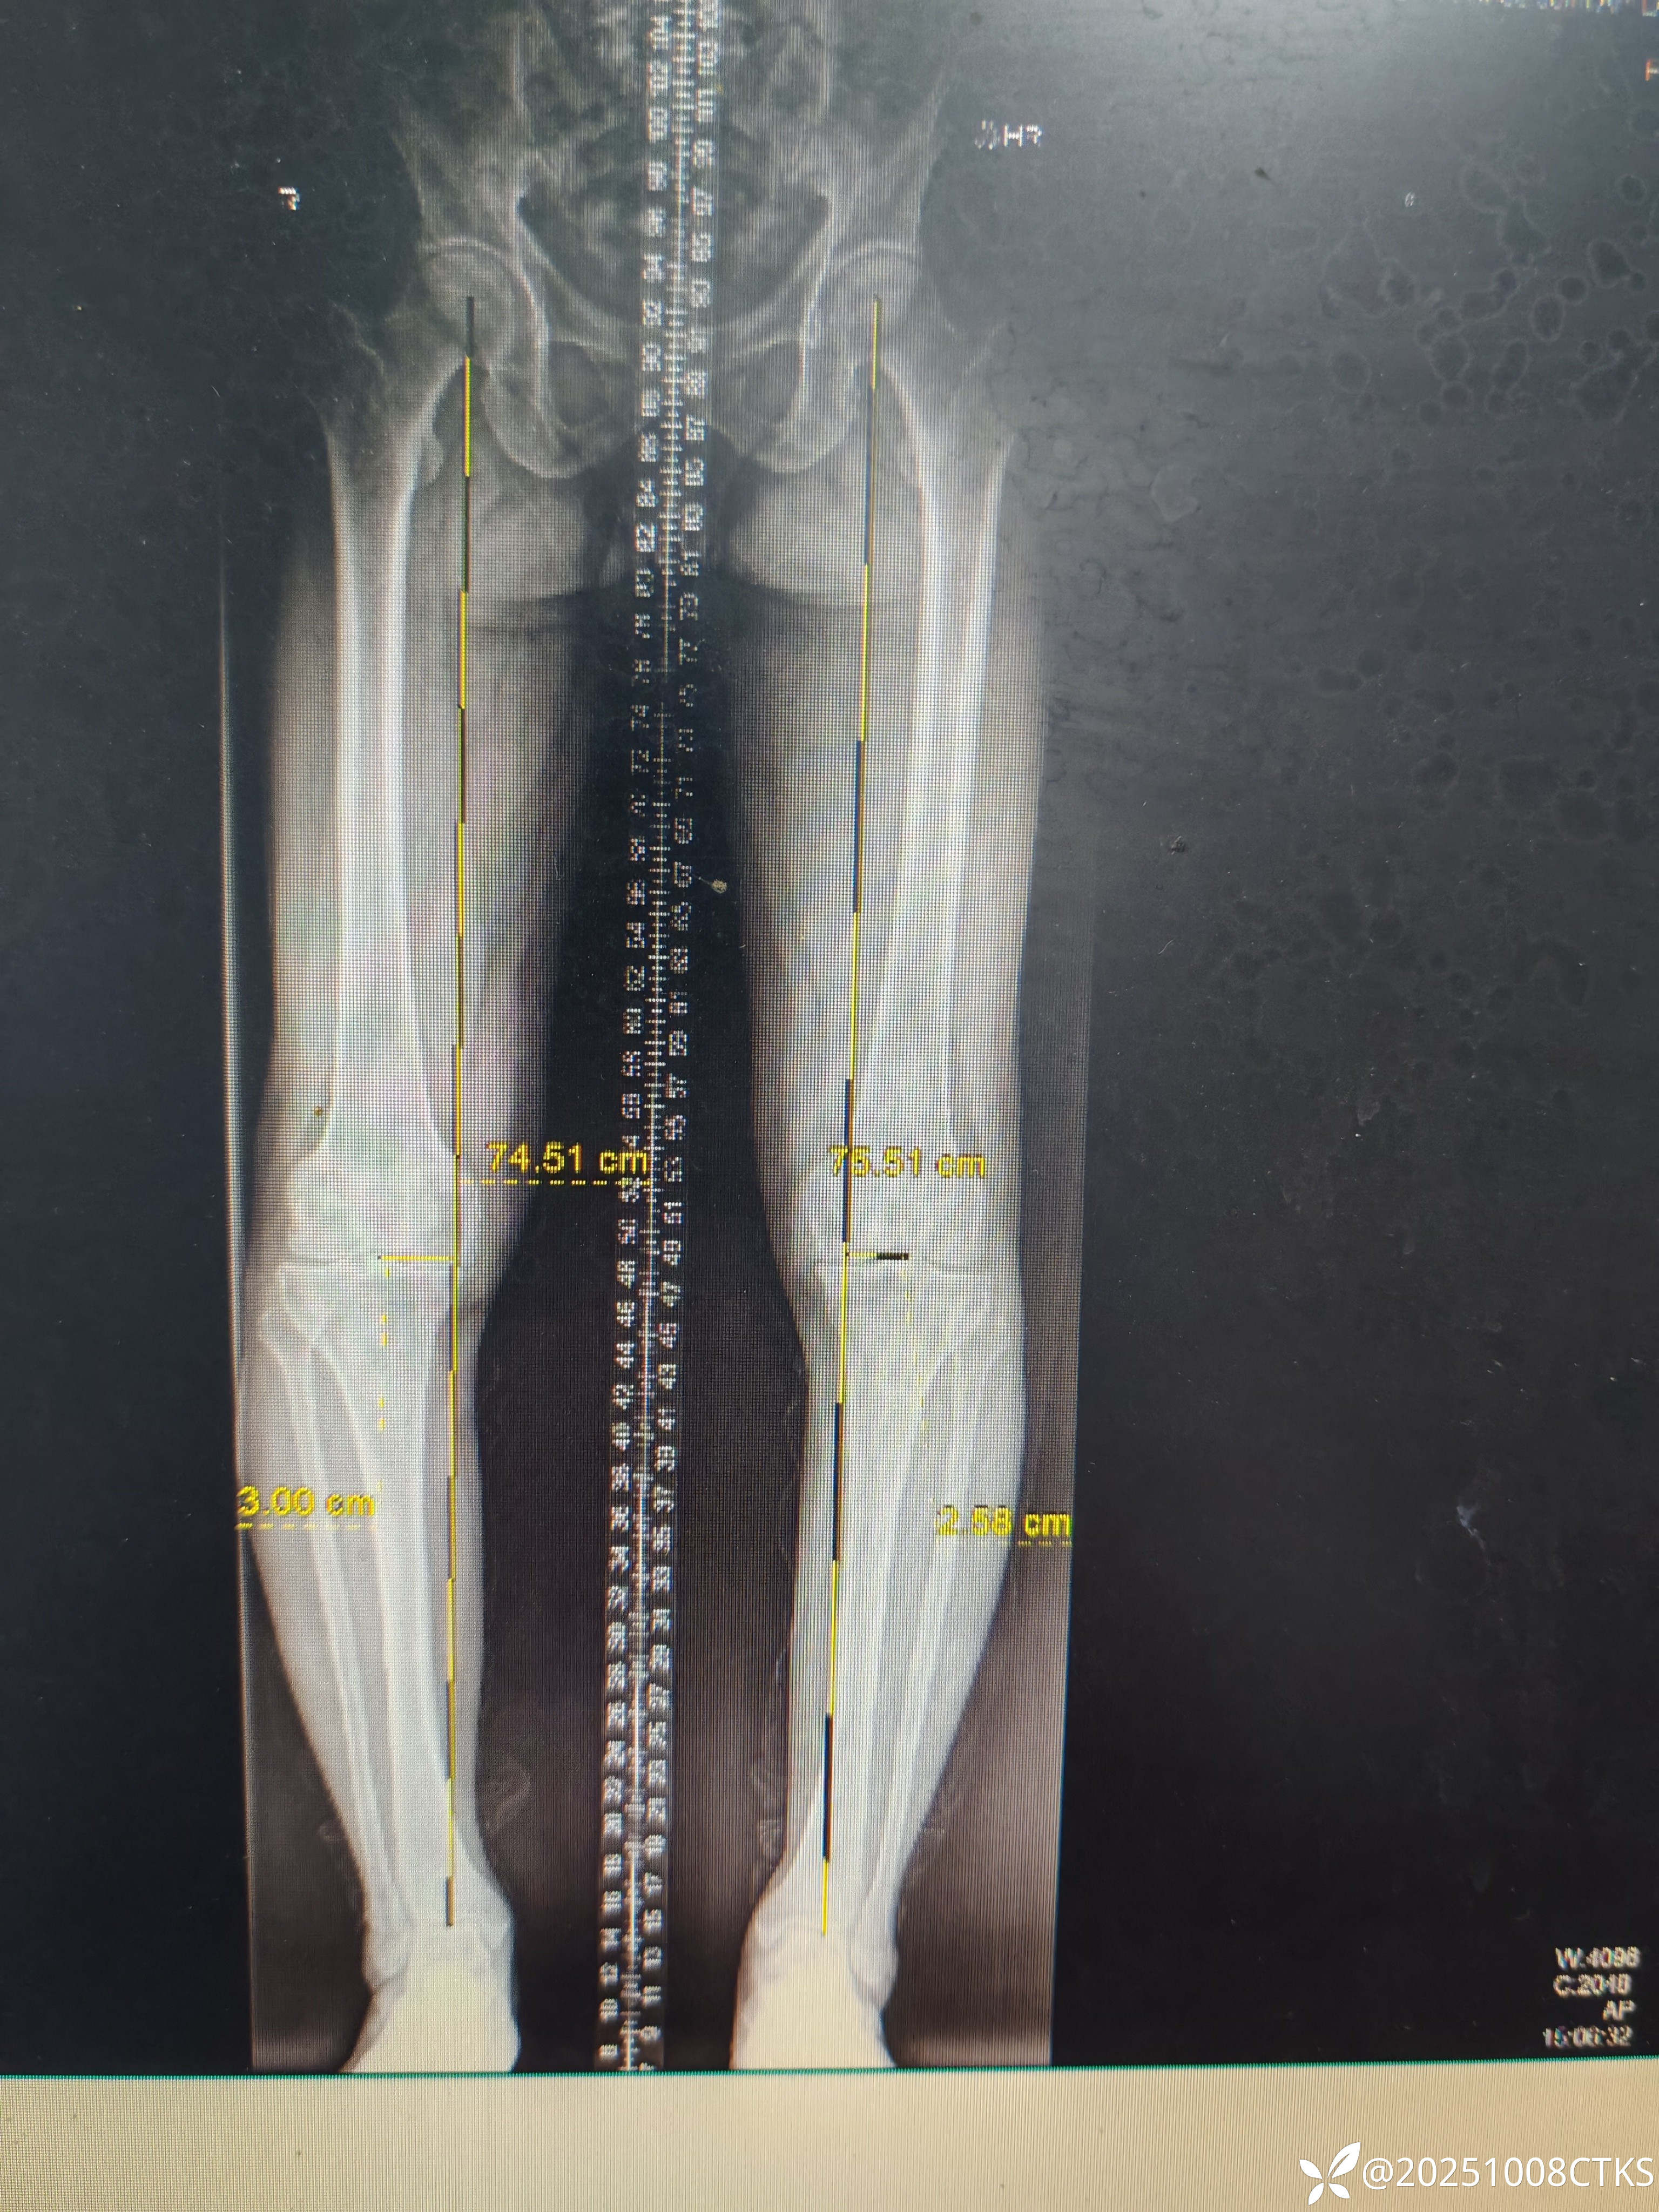

患者,男,69岁,膝关节疼痛十年余,外院建议膝关节关节置换,患者想保守治疗

膝关节退行性变,保守治疗方案有没有好的保守治疗方案,各位老师可以指导一下。